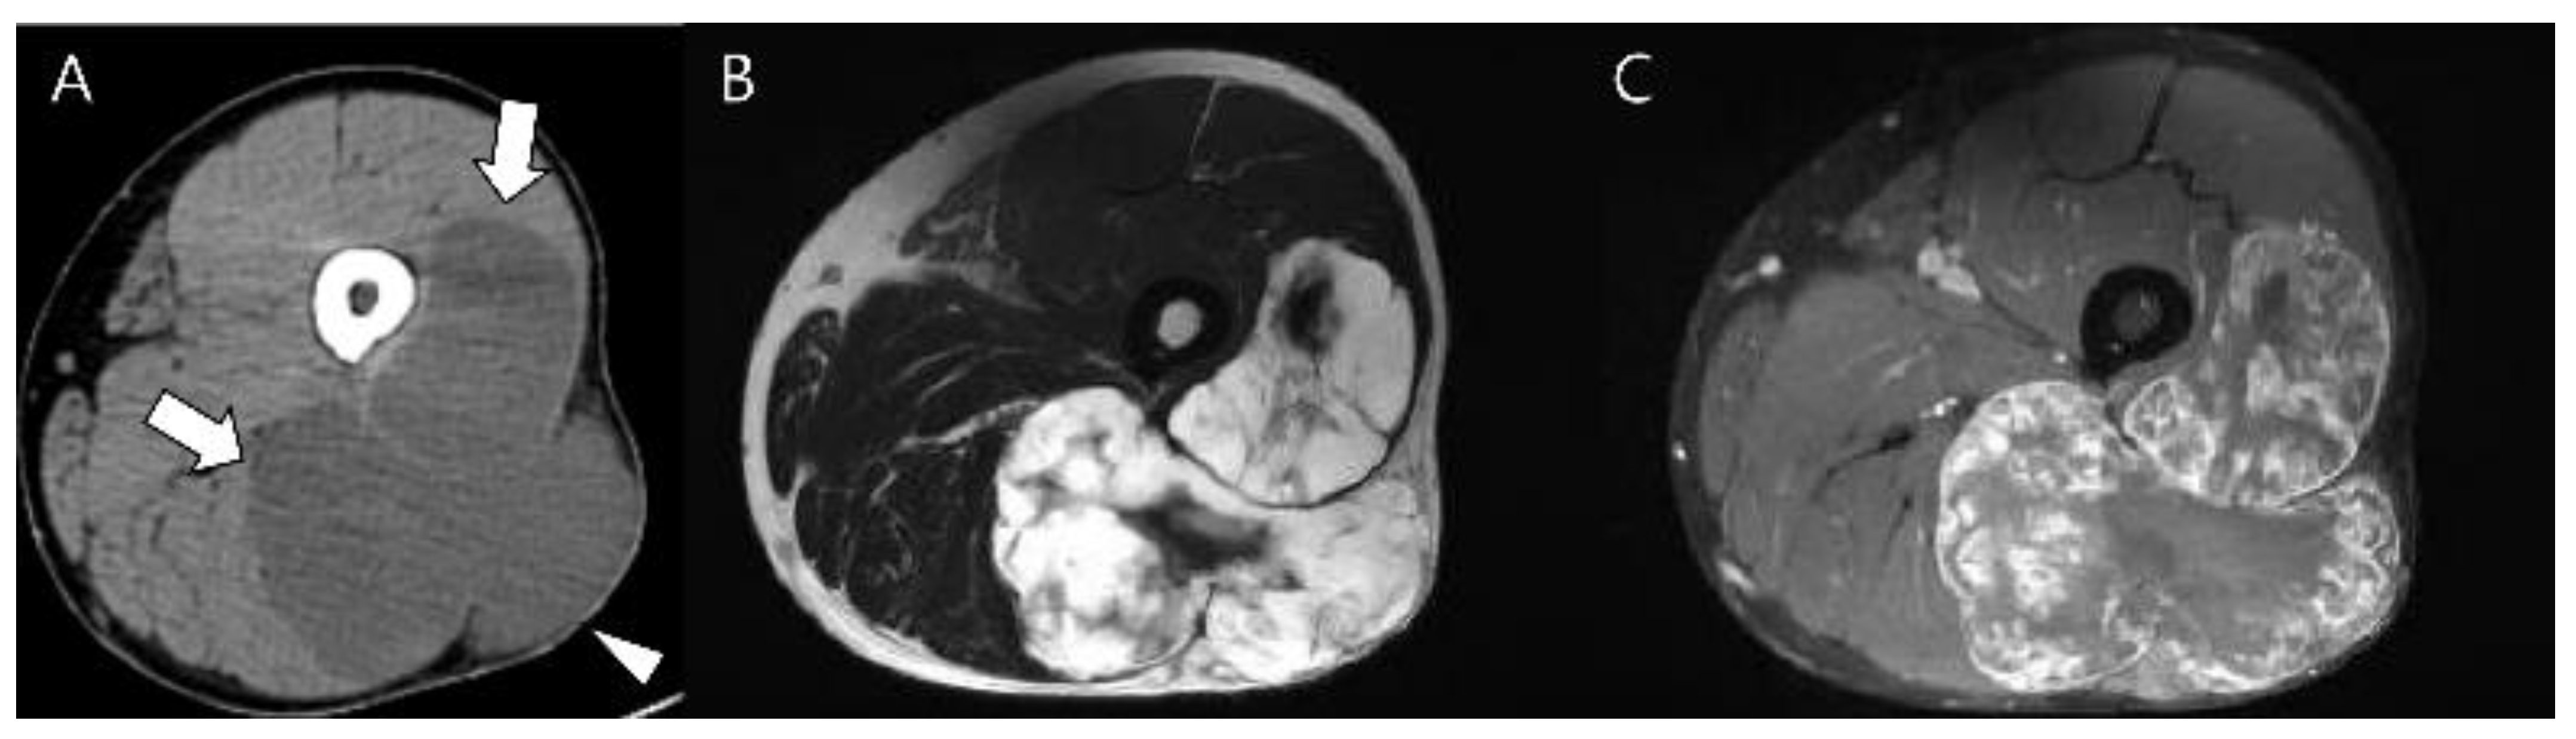

Figure 14.

Extraskeletal myxoid chondrosarcoma of the right thigh in a 46-year-old man. (A) Axial CT scan reveals a lobulated, low-density soft tissue mass (arrows) without chondral-type mineralization between the vastus lateralis and biceps femoris muscles extending to the subcutaneous fat layer (arrowhead). (B,C) Axial T2-weighted and T1-weighted enhanced images show a soft tissue mass with high signal intensity and peripheral rim and septal enhancement.